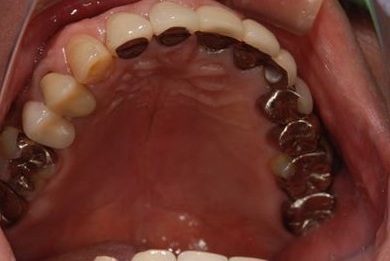

治療後

• 治療後